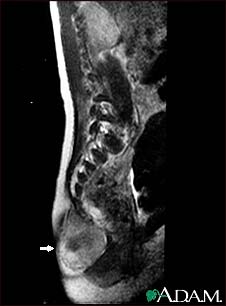

This MRI scan shows a tumor (teratoma) at the base of the spine (seen on the left lower edge of the screen), located in the sacrum and coccyx (sacrococcygeal) area. Teratomas are present at birth and may contain hair, teeth, and other tissues.